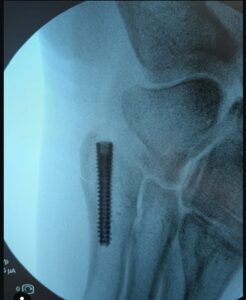

De Belgische wielerster Wout van Aert maakt gestaag vooruitgang in zijn herstel na een ernstige enkelblessure en artsen hebben nu bevestigd dat zijn revalidatie de goede kant op gaat. De 29-jarige liep eerder deze maand een fractuur op tijdens de Zilvermeercross in Mol, waardoor hij een operatie moest ondergaan en zijn veldrijseizoen werd onderbroken.

Het medisch team meldt dat de operatie succesvol is verlopen en dat de eerste fase van het herstel goed verloopt. De zwelling en ontsteking rond de enkel zijn aanzienlijk afgenomen en Van Aert heeft een deel van zijn mobiliteit teruggekregen – een belangrijke indicator dat zijn lichaam goed reageert op de behandeling. Artsen zijn met name tevreden over de stabiliteit van de enkel en merken op dat de pezen en ligamenten rond de fractuur intact en gezond zijn gebleven, wat het risico op complicaties op lange termijn aanzienlijk verkleint.